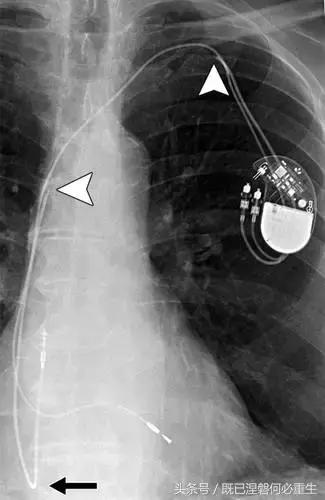

图。 7B 79岁的男性患有电极折断和迁移。

B,大约3年后,电极完全断裂,金属传导碎片(箭头)分离。 远端片段(箭头)已经偏移尾侧,但是由于围绕电极的射线可穿透鞘的约束效应而没有迁移到肺循环中。 引线和中心静脉导管最常见于锁骨和第一肋骨之间断裂,因为它们在臂运动期间被锁骨下肌肉或腱或肋锁韧带压缩[16]。

造成设备故障的最常见的X光检查原因之一是铅断裂。锁骨下静脉经过锁骨下的部位是骨折最常见的位置[16](图7A和7B)。在这个位置的损伤可能发生在导管或导线,并已被描述为锁骨下夹断综合征和锁骨下压溃综合征[16?18]。临床上,骨折的导线通常在患者中产生可以是连续的,间歇的或依赖于患者定位的症状。识别这些状况可能需要挑衅性的动作,例如等长臂锻炼,仰卧或侧向定位或Valsalva。设备检查将显示异常的起搏阻抗(如果绝缘破裂允许导体暴露则减小,如果导体断裂但绝缘完好则增加),感测错误和起搏捕获损失[12]。导线断裂或绝缘损坏可能导致感测或起搏异常。对心律失常的不适当的过感知或欠感应可能导致不适当的治疗,例如抗心动过速起搏和休克治疗,或不适当的抑制治疗。